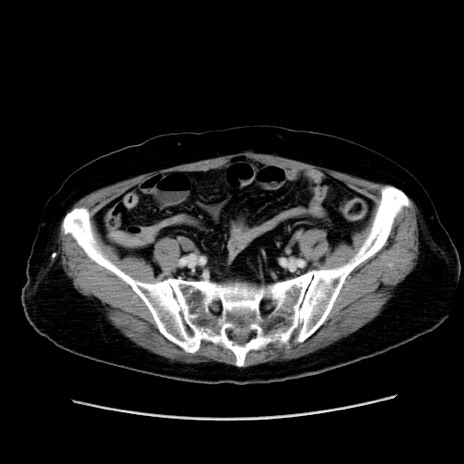

冠状断像

【症例】80歳代女性

【主訴】下腹部痛

【現病歴】約8時間前より下腹部痛の出現あり、救急外来受診。

【既往歴】両側付属器切除

【身体所見】意識清明、下腹部正中に手術痕あり、その部位に一致して圧痛と反跳痛あり。腸蠕動音は亢進。

【データ】WBC 9300、CRP 0.15